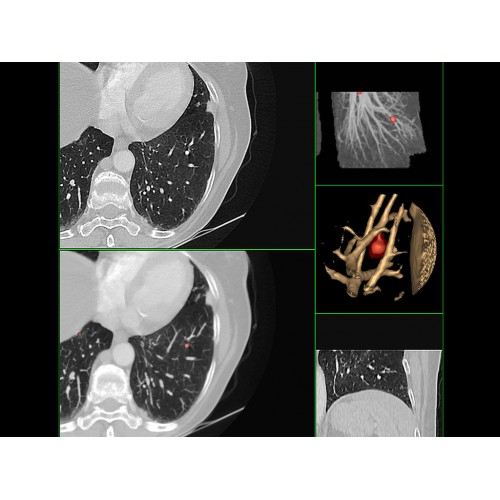

Современный КТ-аппарат с высокой скоростью сканирования и точной визуализацией. Обеспечивает детализированные снимки для надежной диагностики. Экономичное энергопотребление и удобное управление повышают эффективность работы. Отличный выбор для медицинских учреждений любого уровня.

Современный КТ аппарат GE Optima CT520 – это инновационное оборудование для точной и быстрой диагностики. Он сочетает в себе передовые технологии, надежность и удобство использования, что делает его востребованным в медицинских учреждениях различного профиля.

• Высокое качество изображения благодаря усовершенствованной системе реконструкции данных.

• Сниженная лучевая нагрузка на пациента без потери информативности снимков.

• Широкая область применения: от неврологии до кардиологии и онкологии.

КТ аппарат GE Optima CT520 используется для диагностики широкого спектра заболеваний:

Онкология

• Раннее выявление новообразований и контроль эффективности лечения.

• Планирование лучевой терапии с высокой точностью.